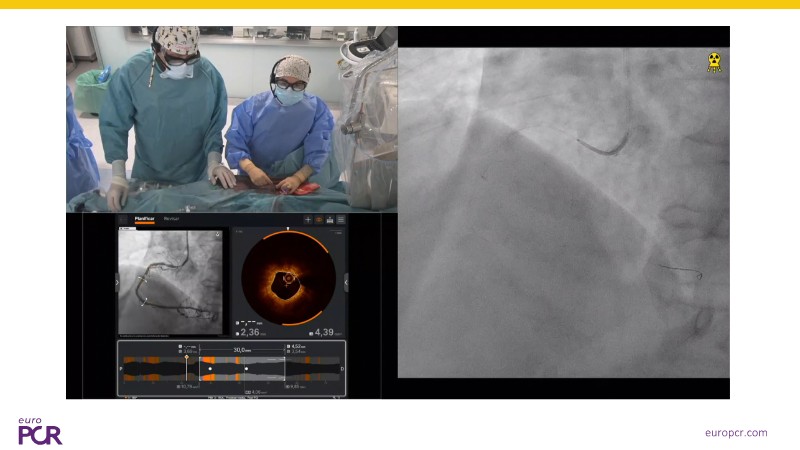

Watch this EuroPCR 2025 session to learn how intravascular lithotripsy (IVL) is transforming the management of coronary artery calcification (CAC). Discover the new CALC roadmap, a comprehensive framework guiding device selection and treatment strategies based on calcium burden, anatomy, and patient gender. Follow a real-world clinical case demonstrating how to optimize treatment pathways using IVL as a first-line approach, supported by exciting new clinical data from multiple studies. Gain practical insights on sizing IVL balloons with intracoronary imaging to maximize procedural success and safety, and explore how this technology can improve outcomes by simplifying calcium modification during PCI.

- To learn with a real-world clinical case how to optimise treatment pathways for CAC, supported by new clinical data

- To explore the role of intravascular lithotripsy as a first-line treatment strategy for managing coronary artery calcification and its impact on procedural outcomes